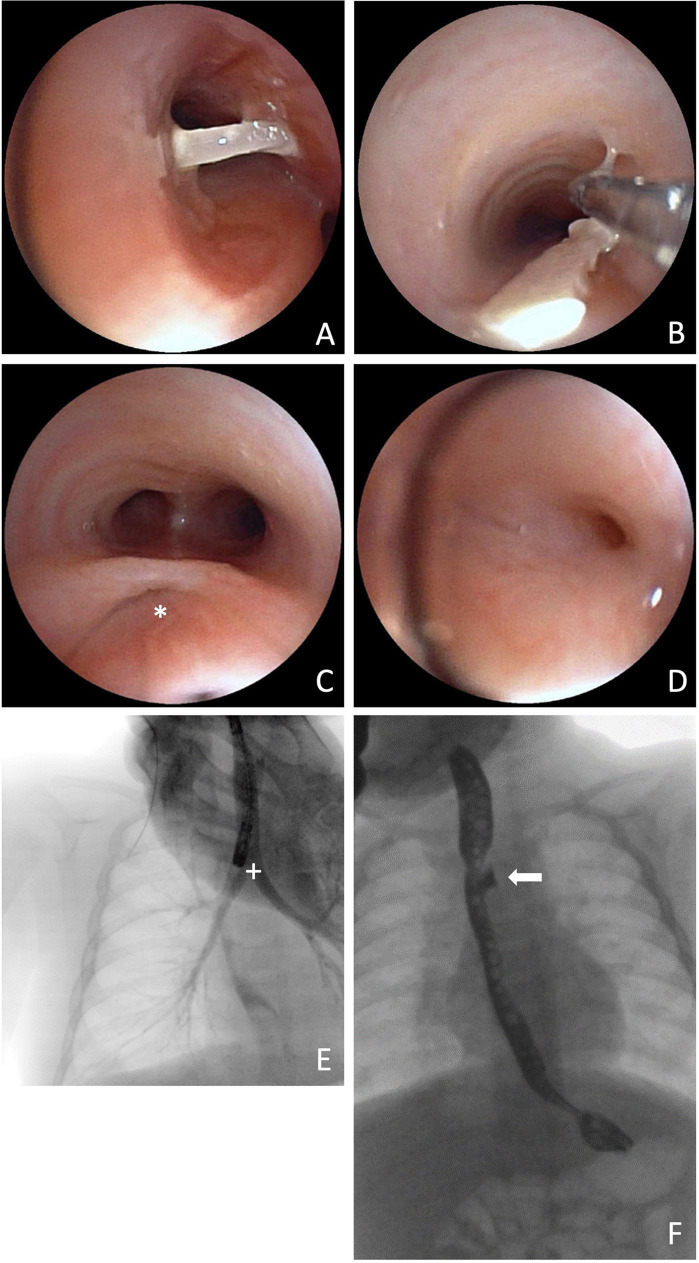

Case report: A term boy (GA: 42 + 1 weeks; BW: 3,110 g) underwent thoracoscopic TEF repair for Type C EA. We ligated the fistula using a polymer clip followed by primary esophageal anastomosis on the second day of life. At ten weeks of age, we readmitted the infant due to recurrent bronchitis and episodes of postprandial coughing. Flexible bronchoscopy revealed that the polymer clip, previously employed for fistula closure, had migrated into the right main bronchus and was subsequently retrieved. Despite clip removal, persistent coughing prompted further evaluation, revealing a recurrent TEF on contrast esophagography. An interdisciplinary team successfully obliterated the recurrent fistula using endoscopic chemocauterization with trichloroacetic acid (TCA) via rigid bronchoscopy. Additionally, due to a developing anastomotic stricture, the patient required four balloon dilations and a single triamcinolone injection. At the three-year follow-up, the patient is eating well and thriving normally.